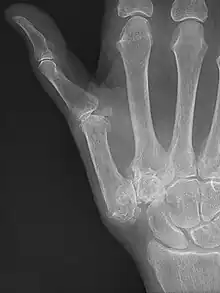

![]() | |

| Osteoarthritis of the CMC joint | |

| Diagnostic method | Based on symptoms, X-rays[4][1] |

Risk factors include previous injury, excessive use, obesity, and inflammatory joint disease.[4][6] The underlying mechanism involves a breakdown of the cartilage within the carpometacarpal (CMC) joint.[5] Diagnosis is generally based on symptoms and X-rays.[4][1]

Diagnosed is based on symptoms.[7] Xrays can confirm the diagnosis and the severity. Other diagnoses in this region include scaphotrapezial trapezoid arthritis and first dorsal compartment tendinopathy (De Quervain syndrome) although these are usually easy to distinguish.